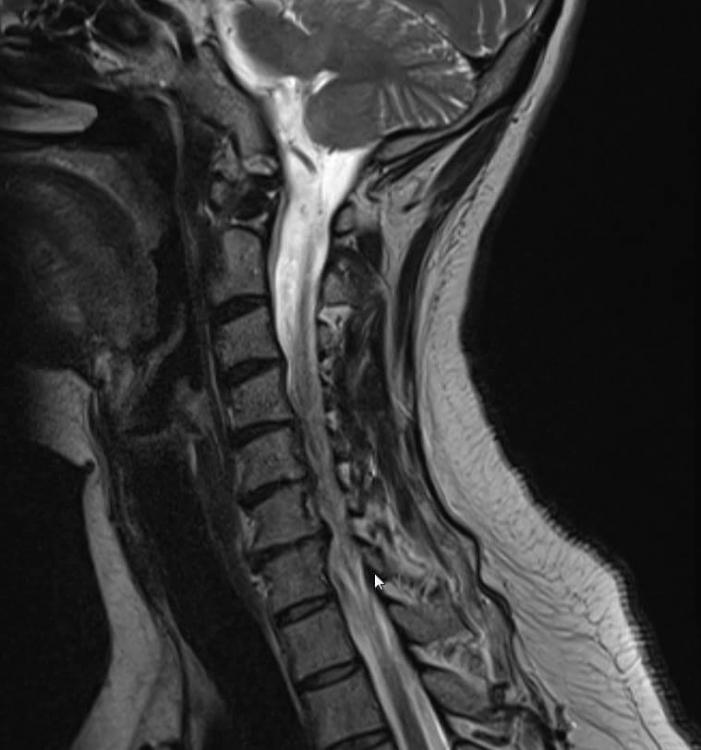

Möglicherweise sind es auch mehr diese Osteochondrosen die auf den Nerv drücken? Ich habe mal zwei MRT Bilder angehängt.

MRT1.jpg

MRT2.jpg

Ich kann dich beruhigen, dein Nerv ist mit Sicherheit nicht abgestorben;) Es ist nämlich so. Dein Nerv wird ebenfalls von kleinen kapillaren versorgt, das sind die kleinsten Blutgefäße. Wird der Nerv so stark gedrückt das seine Versorgung nicht mehr gewährleistet ist wird er nicht nur mit einem krippeln und Taubheitsgefühl reagieren sondern mit Schmerzen. Das wäre eine Bedrohung für den Nerv, und die roten Warnlämpchen (Schmerzen) springen an. Bevor dein Nerv abstirbt würden nach Sensibilitätsstörungen und krippeln, motorische Ausfälle folgen i.Sinne von Kraftidefizit und Lähmungen. Um das zu verstehen muss man wissen wie ein Nerv im Querschnitt aussieht. Im Inneren befinden sich geschützt von den Sensiblen Fasern die Motorischen. Diese Sind dafür zuständig daß wir überhaupt unsere Muskulatur anspannen Können. Um Ihnen liegen wie eine Hülle die Sensiblen Fasern, die für das Gefühl zuständig sind, und auch Schmerzreize die über Rezeptoren ins Gehirn weitergeleitet werden liegen ausen. Das ist sinnvoll. Die motorischen Fasern sind letztendlich viel wichtiger wie die Sensiblen Nervenfasern. Sobald die Hülle komprimiert wird kommt es also zunächst zu krippeln und Taubheitsgefühlen. Geht die Kompression weiter oder ist sie heftig daß sogar Motorische Fasern im Inneren gedrückt werden dann kommen erstmal Schmerzen, meist auch brennende Schmerzen, die diese Gefahr signalisieren. Zum Schluss kommt es dann zu Lähmungen. Trotzdem sollte so schnell wie möglich deine Nervenwurzel entlastet werden. Was deine Therapeutin gemacht hat war eine HWS-traktion. Man zieht die HWS quasi in die länge. Dies kann bei akuten BSV sicherlich für Entlastung sorgen, aber es gibt effekivere Methoden da Der Nervenkanal nur solange erweitert wird wie eine Traktion durchgeführt wird danach ist der Zustand aber wieder wie vorher. Auf dem oberen  MRT bild kann man nun sehr schön deine BSV in den entsprechenden Wirbelsegmenten sehen und deine Beschwerden nachvollziehen. Hier muss unbedingt das ausgetretene BSmaterial wieder zurückgebracht werden. Ich habe bei meinen Pat.gute Erfahrung gemacht mit der Mobilisation der HWS in die Extension (Das ist die überstreckung) der HWS.  Haben deine Therapeuten auch den Nerv mitbehandelt? Dies wäre auch eine wichtige Sache, über sog. N.radialis mobilisation zusätzlich die Nervensymptome zu reduzieren, denn  auch der Nerv der in Mitleidenschaft gezogen ist, muss sich ja wieder regnerieren. Oft ist das NErvensystem noch unflexibel und das NErvengleitlager verklebt. Deshalb sollte 1.die Ursache in der HWS behandelt werden und 2. Eine Symptombehandlung der betroffenen Nerven mit in der Behandlung Eingebunden werden